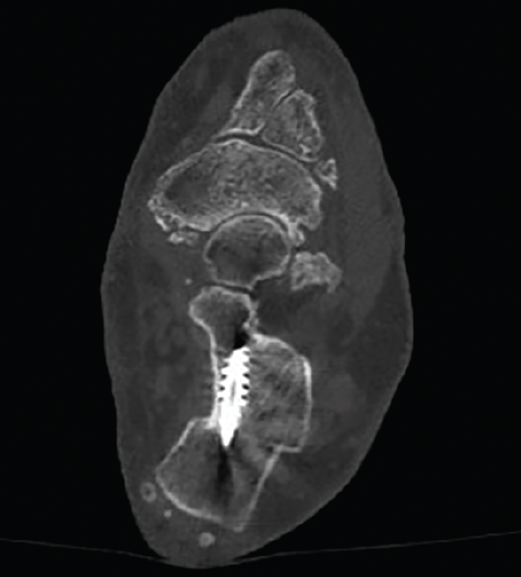

Figura 11. Detalle de la osteotomía en la tomografía computarizada a los 3 meses.

Los procedimientos que acompañan a la OCP en la corrección de las deformidades suelen marcar el tiempo de descarga e inmovilización. Cuando la osteotomía es el único procedimiento óseo de la corrección, se autoriza una carga protegida con bota de tipo Walker e inicio de ejercicios de flexoextensión de tobillo a las 4-5 semanas, para posteriormente iniciar progresivamente la carga completa 2 semanas después (Figuras 10 y 11).

Una vez comprobado el suficiente desplazamiento en la proyección axial del calcáneo, se fija la osteotomía con 2 agujas de Kirschner sobre las que se introducirán 2 tornillos canulados de un tamaño de entre 5,5 y 7 mm, y se verifica su correcta colocación en la visión lateral y axial fluoroscópica (Figura 9).

Figura 9. Imágenes fluoroscópicas de fijación de la osteotomía con agujas de Kirschner y tornillos canulados en anteroposterior y axial del calcáneo.